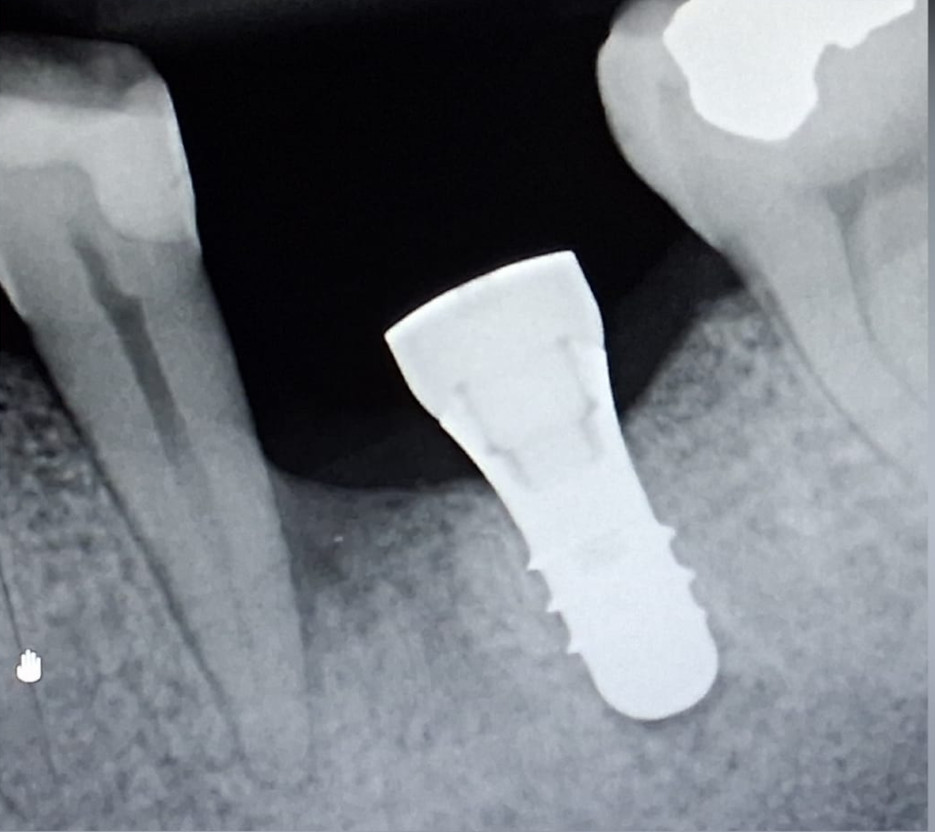

Ormai da molti anni (circa 35) dove manca un dente si inserisce una radice artificiale

(impianto) su cui successivamente, viene posizionata una corona (capsula).

Anche laddove c’è poco osso è possibile adottare, valutando caso per caso, procedure

che permettano comunque l’inserimento dell’impianto.

Dopo